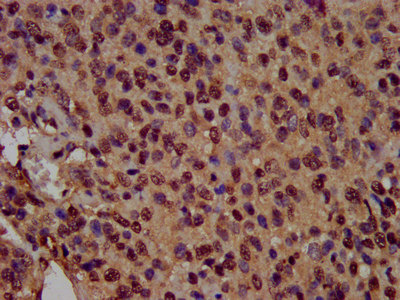

IHC image of CSB-PA010418OA14nsucHU diluted at 1:100 and staining in paraffin-embedded human glioma performed on a Leica BondTM system. After dewaxing and hydration, antigen retrieval was mediated by high pressure in a citrate buffer (pH 6.0). Section was blocked with 10% normal goat serum 30min at RT. Then primary antibody (1% BSA) was incubated at 4°C overnight. The primary is detected by a biotinylated secondary antibody and visualized using an HRP conjugated SP system.